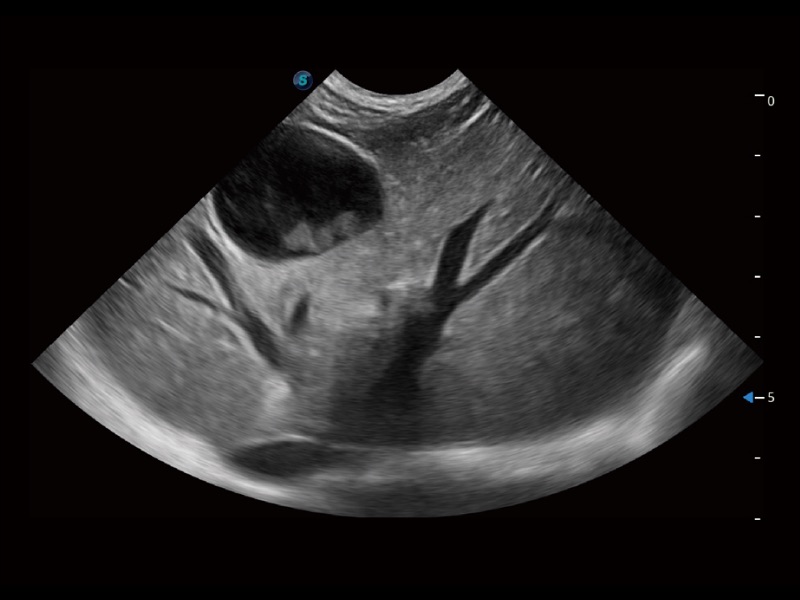

通过创新的 Matrix E自适应滤波器和超长时间域算法,极大提升超低速微细血流的检出能力,同时更精准地滤除软组织和噪声信号,为兽用医生提供以往无法通过常规血流获得的疾病诊断信息。

通过色彩血流和实时宽景相结合,可观察到完整的静脉或动脉的血流,方便医生检查。实时扫查过程中,如有任何操作失误也可以很容易地进行回扫擦除,而不会中断扫查。

为精细结构及组织边缘提供高清晰度的图像和更大的成像视野。帮助减轻医生的用眼疲劳,快速精准获得测量的数据。